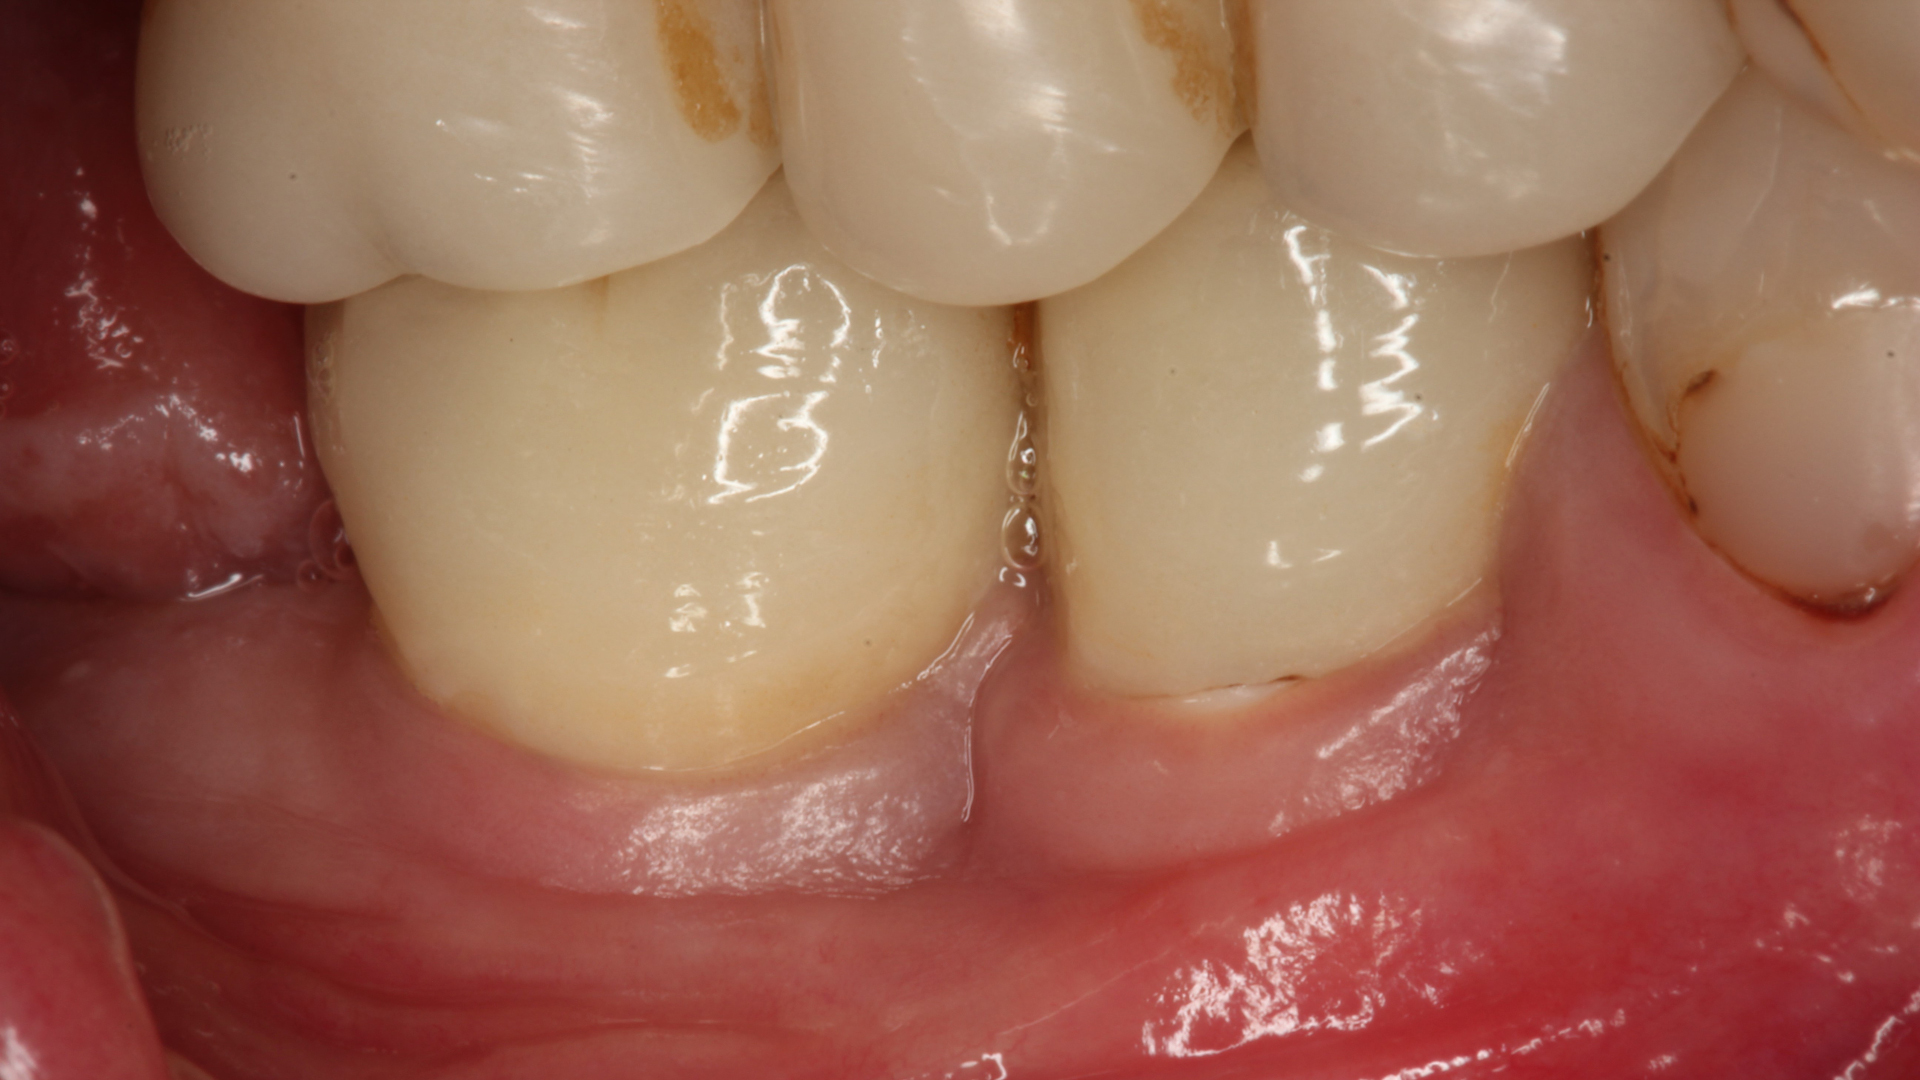

Dr Sofia Karapataki and her team monitored 39 dental implant patients with 91 Patent implants over five to 12 years and observed no cases of peri-implantitis or implant loss. (Image: Karapataki et al. 2023)

Dr Sofia Karapataki, an implantologist from Greece and the lead researcher of the study, explained that in the study researchers from the Medical University of Graz in Austria and Heinrich Heine University Düsseldorf in Germany had monitored 39 dental implant patients with 91 Patent implants over five to 12 years. Just 7.7% of patients (accounting for 9.9% of all implants) showed signs of peri-implant mucositis, she said, adding that marginal bone loss (MBL) exceeding the first thread was observed at 35.0% of mesial sites and 27.4% of distal sites. A smaller number of sites showed MBL beyond the first thread but not past the third, and there was only one instance of pocket deepening to 4 mm with bleeding, yet MBL was under 1.65 mm. There were no cases of peri-implantitis or implant loss.

According to Dr Glauser, the study confirms once again the efficacy of the Patent implant system’s potential to maintain bone stability after tooth replacement. He attributed the fostering of mature, healthy, dense and stable soft tissue witnessed by the study to the soft-tissue adhesion achieved by the Patent system in the transmucosal region, adding that a strong and intimate contact between the soft tissue and the implant surface makes it difficult for bacteria to penetrate the tissue. “The goal should be to prevent peri-implantitis from the outset—after all, prevention is the best therapy,” Dr Glauser remarked.

Research shows that nearly half of dental implant patients experience peri-implant mucositis, often leading to peri-implantitis, which affects 22% of patients and is a leading cause of implant failure. (Image: Karapataki et al. 2023)